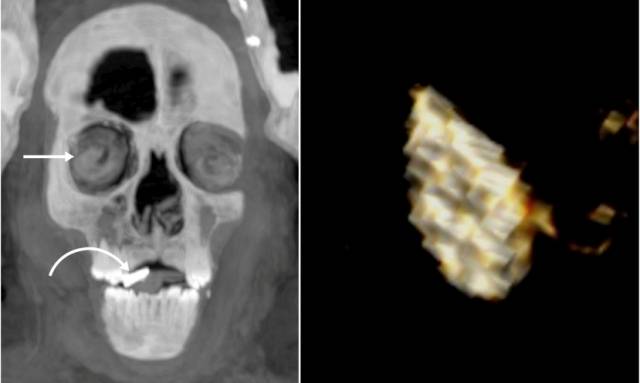

특히 CT 사진에서는 소년의 입과 가슴 등에서 총 21가지 모양의 다양한 부적 49개가 발견됐다.

대부분 금으로 만들어졌고, 준보석이나 구운 점토, 도자기 등으로 제작한 부적도 있었다.

그중 ‘황금 혀’ 부적은 사후세계에서 말을 할 수 있도록 돕기 위한 것이고, ‘이시스 매듭’ 부적은 이시스 여신의 보호를 의미하는 것이라고 연구팀을 풀이했다.

망자의 심장 위치에 놓는 풍뎅이 모양의 황금 장식품 ‘하트 스카라베’를 비롯해 호루스의 눈, 타조 깃털 부적 등도 몸 곳곳에서 찾아볼 수 있었다.